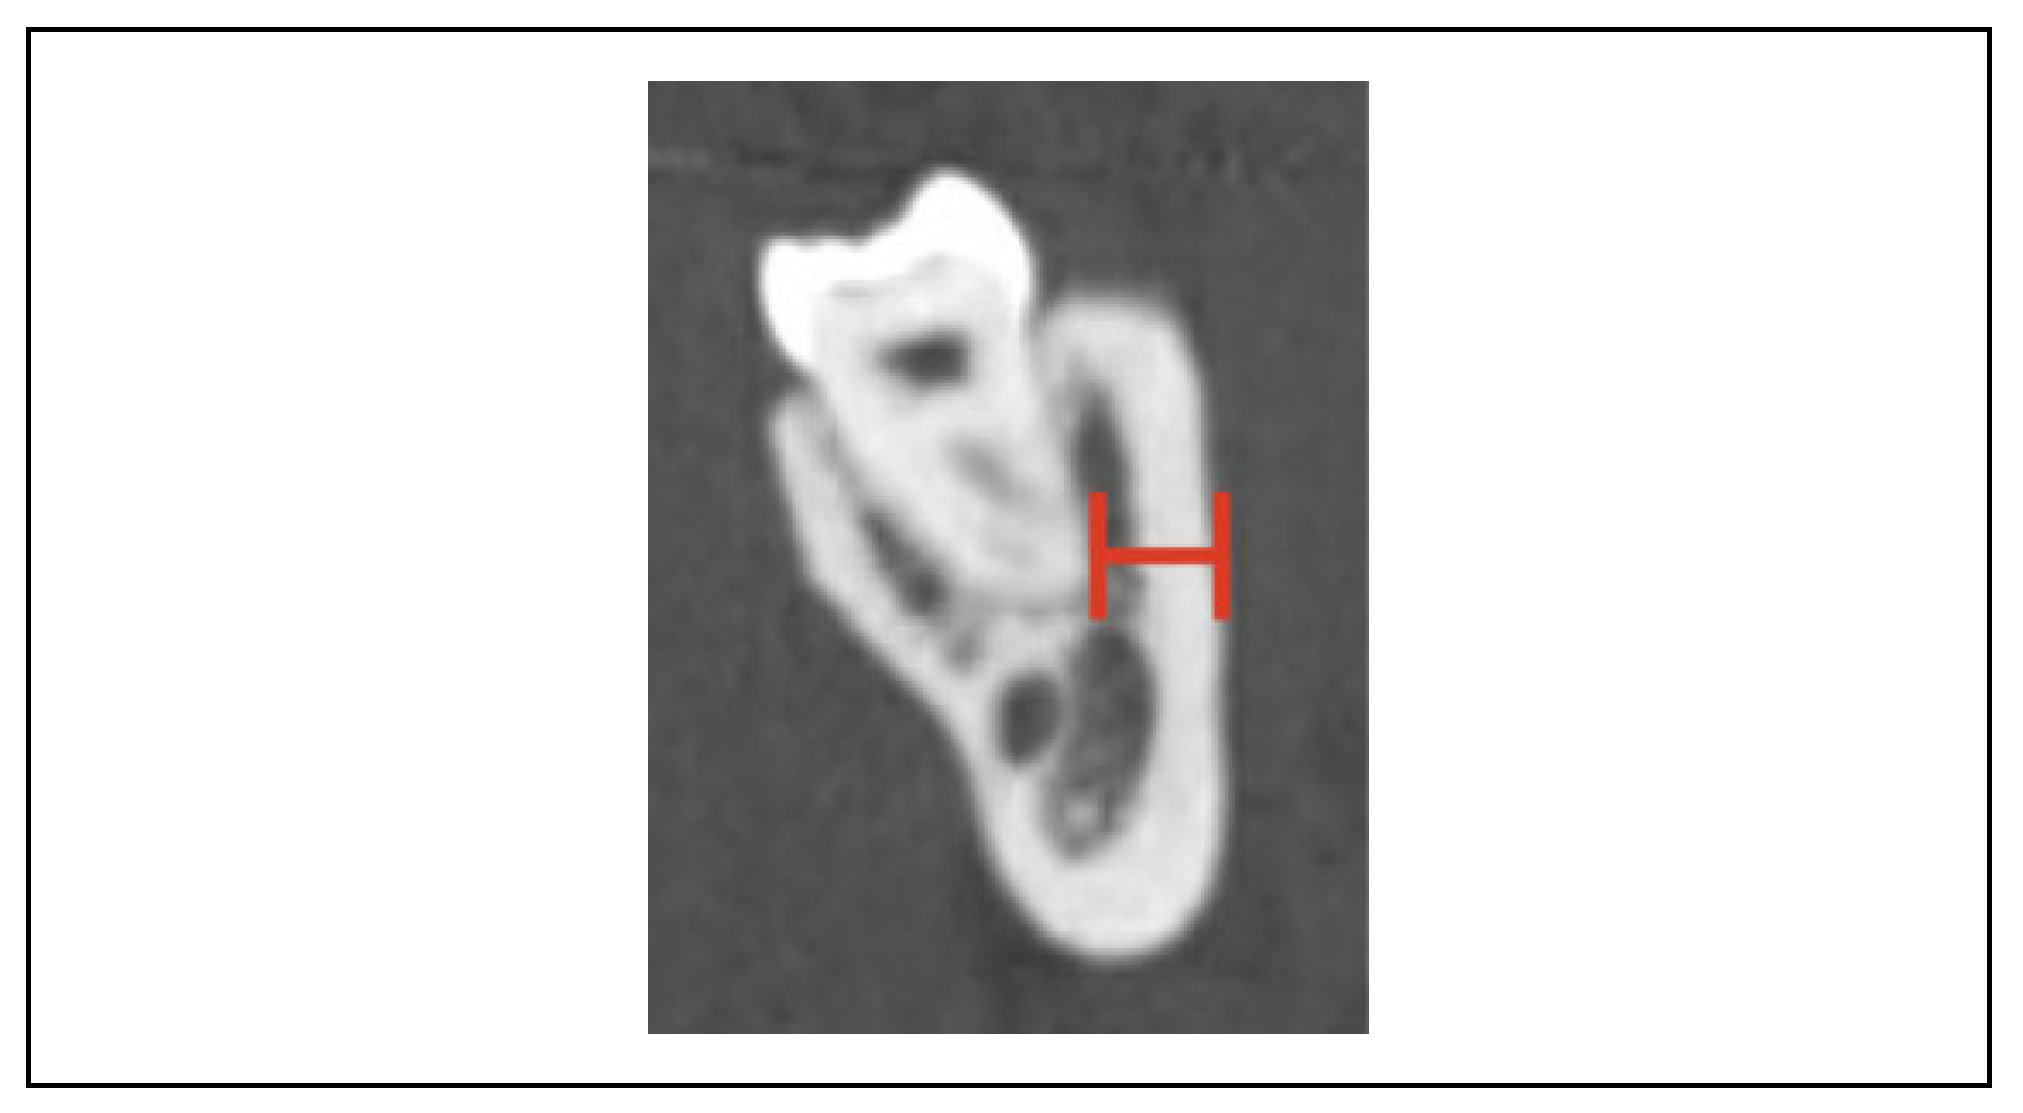

Is There a Safe Zone for Lateral Border Fixation of Mandibular Angle Fractures?

2. Methods

3. Results